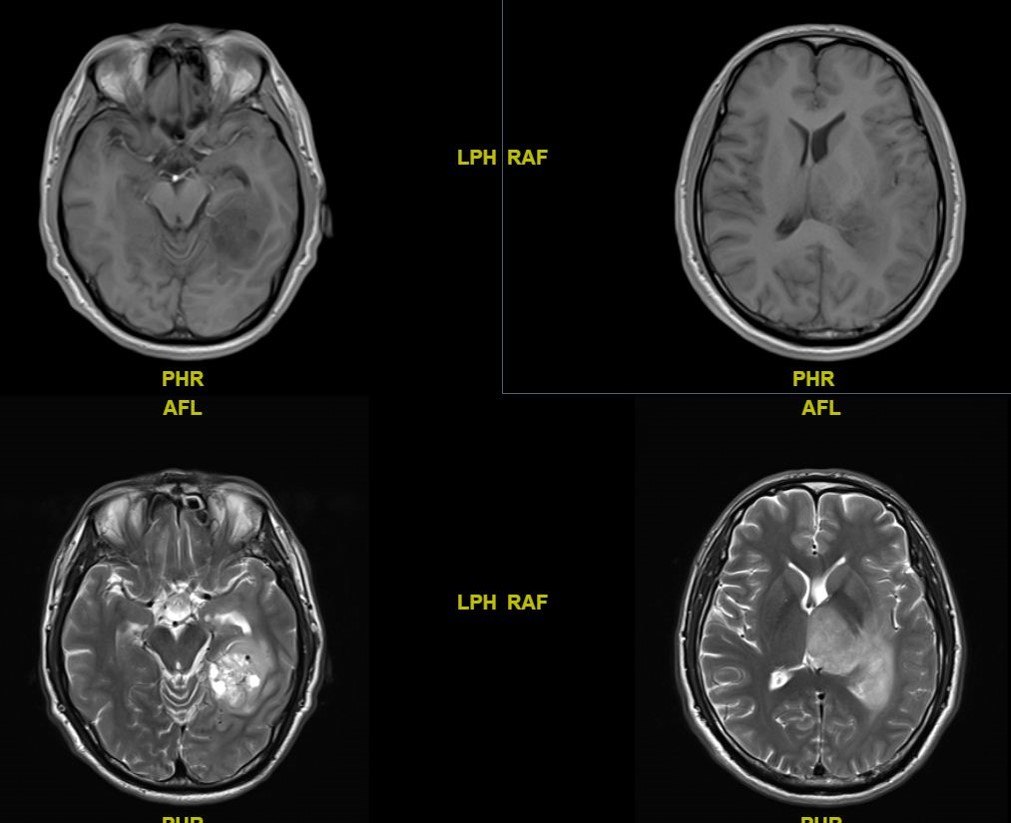

头颅MRI示:左侧颞叶深部天幕上缘病变,T1低信号,T2混杂信号,不均匀强化;左侧丘脑病变,T1等信号,T2高信号,未见明显强化。

术后病理提示:左侧天幕缘:胶质母细胞瘤(WHO IV级,IDH野生型);左侧丘脑:弥漫性胶质瘤(WHO II级)。

该患者为中年男性,因头痛头晕2个月就诊,头颅MRI示:左侧丘脑、左侧枕叶近胼胝体压部、四脑室周边异常信号改变,TI呈低信号,T2呈高信号,无明显强化。

术后病理提示:左侧枕叶:弥漫性星形细胞瘤(WHO III级;IDH野生型);左侧丘脑:胶质母细胞瘤(WHO IV级;IDH野生型)。